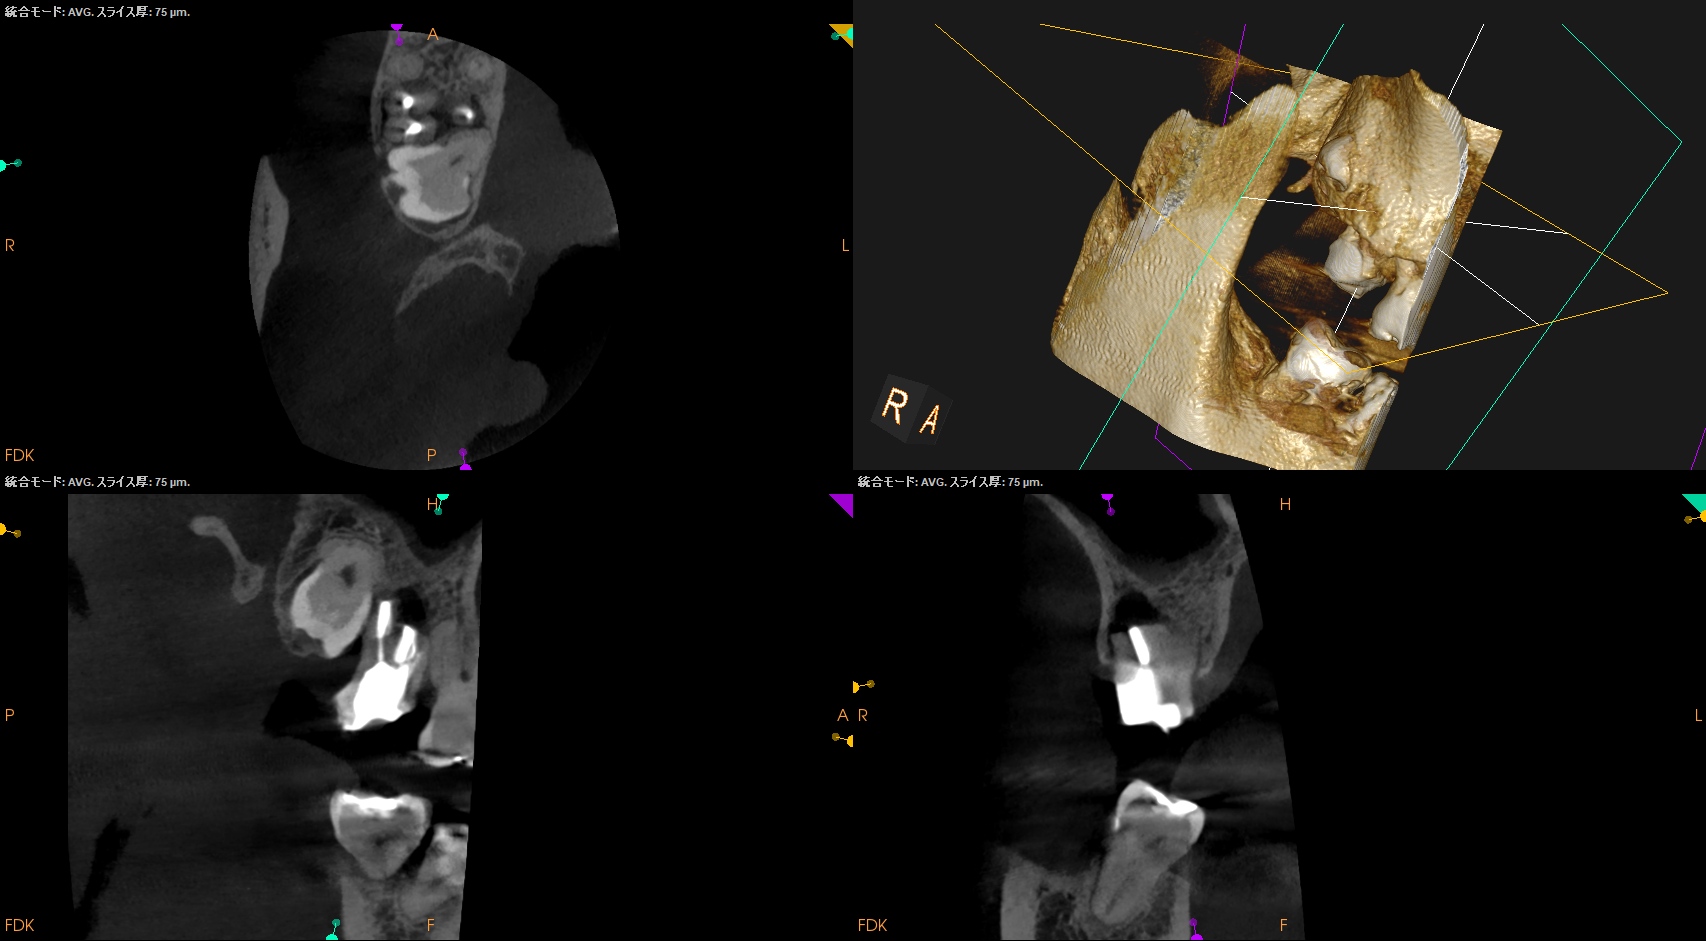

#2 Intentional Replantation(2025.12.12)

脱臼して抜歯しているので再植は難しいであろう…という印象を抱かさせるような抜歯作業だ。

抜歯窩を確認した。

ここからは口腔外作業になる。

メチレンブルーで染め出してRoot resectionした。

切断部分をメチレンブルーで染め出した後に逆根管形成した。

ファイルが破折しているMBから折れたファイルを取り出そうとするが困難であった。

仕方がないのでそのままにして逆根管形成を進めていった。

逆根管充填した。

術後にPAを撮影した。

折れたファイルはIntentional Replantationの術式では取れなかった。

が、それをあえて取ろうという考えは私にはない。

MB

DB

P

問題はないだろう。